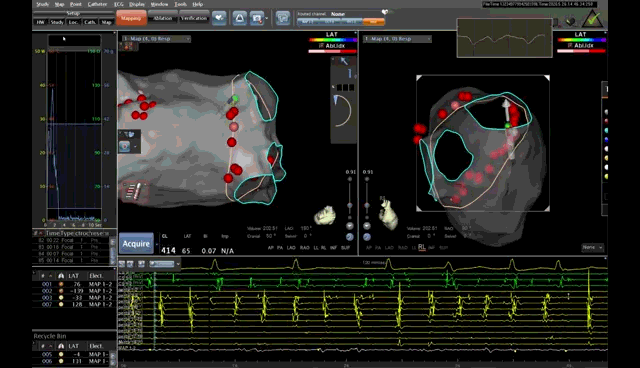

AI房颤精准消融病例:林某,男,80岁,阵发性心悸8年入院,诊断为“阵发性房颤”。由于心悸频发,心情烦躁,夜间经常惊醒,患者不堪其扰,反复住院。心血管病科栾杰男主任认真查看患者后,建议采用射频消融术治疗。但由于患者高龄,合并糖尿病及冠心病,须做好充分准备,手术须认真谨慎,不做过多操作,达到安全精准治疗。术者匡荣仁副主任医师与患者及家属充分交流后,术前行左房增强CT排除心房内血栓,并CT三维重建了解肺静脉解剖。术中局麻下穿刺房间隔成功后,在Carto 3系统下建模,模型与CT三维重建效果图吻合。随后使用ST(压力)消融大头行环肺静脉消融术,根据患者状况AI指数控制在前壁400-450之间、后壁350-400之间。术前患者心电图为房颤律,消融过程中房颤转为窦律。经过验证肺静脉电位隔离成功,手术过程顺利,无过多消融,患者耐受度良好。

术中射频消融效果图(红点为消融点)